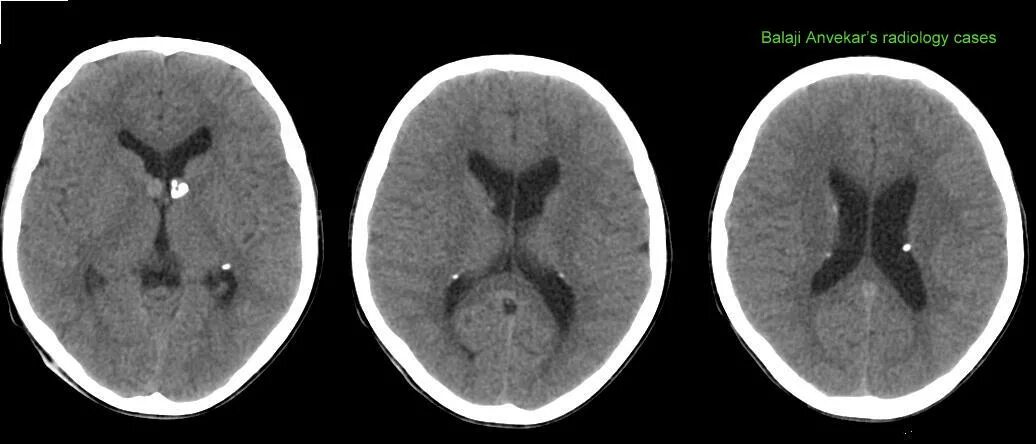

Туберкулезный склероз